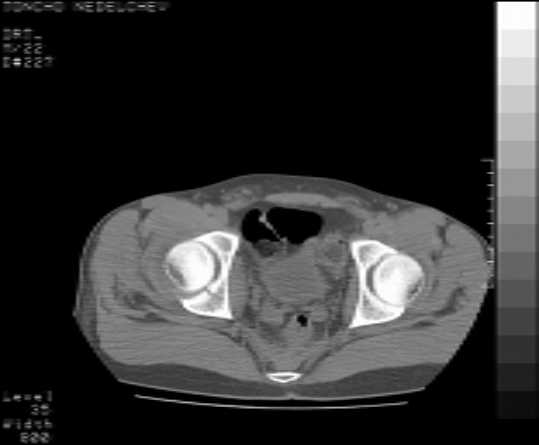

Here are some more axial images. What is your opinion as for the timing of the operative treatment?

Yordan! In this case position of bone fragments is quite good. We

prefer to use miniinvasive technique. We fix posterior column by can. screw and put 3mm pin with distal thread to the anterior column. Next day after the surgery he may start walking with crutches. 3 month after the surgery we remove the pin. In cases of maleolar fractures we use